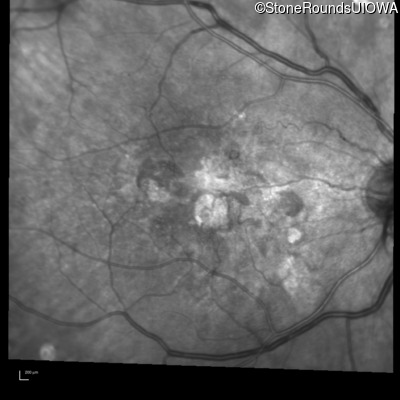

Visit at age: 60 years (Visit 3)

Infrared Fundus Photograph - Right - 20/150

Exemplar